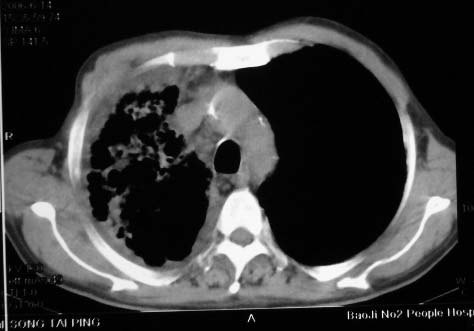

影象表现:右肺上叶大片状、网格状及索条致密影,蜂窝影,其内参杂斑点状小结节,密度不均匀,内见含气支气管像,纵隔内见肿大淋巴结.

抗炎10天后无好转出现胸水,考虑:肺结核合并间质纤维化

抗感染病变无明显改善,右上叶大片状增弥不均匀病灶,夹杂网状及支气管充气像,肺门纵隔淋巴结肿大,右侧胸腔积液。考虑1混合感染伴肺间质改变[警惕特殊感染,如真菌]。2细支气管肺泡癌。建议结合临床及进一步检查[如痰,胸水脱落细胞检查及支气管镜检灌洗或穿刺活检

影象表现:右肺上叶大片状、网格状及索条致密影,蜂窝影,其内参杂斑点状小结节,密度不均匀,内见枯枝样含气支气管像,纵隔内见肿大淋巴结.胸膜广泛增厚,前胸壁似受累.少量胸腔积液.纵隔内淋巴结的直径>1.5cm.右侧胸廓体积缩小.考虑:1 肺结核合并间质纤维化 2 细支气管肺泡癌

右肺上叶大片状、网格状及索条致密影,蜂窝影,其内参杂斑点状小结节,密度不均匀,内见枯枝样含气支气管像,纵隔内见肿大淋巴结.胸膜广泛增厚,前胸壁受累增厚.少量胸腔积液.纵隔内淋巴结的直径>1.5cm.右侧胸廓体积缩小.考虑: 细支气管肺泡癌并肺内癌性淋巴管炎。